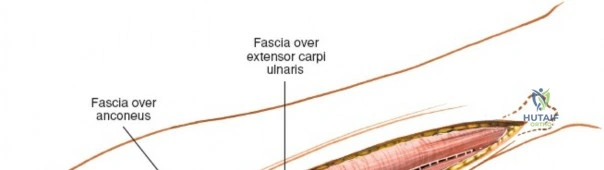

Superficial Surgical Dissection and Internervous Plane

Incise the deep fascia of the forearm in line with the skin incision. The initial goal is to identify the medial border of the brachioradialis as it courses down the forearm. It is a common pitfall to search for this border too far laterally. At the level of the elbow, the brachioradialis is expansive and extends almost halfway across the anterior forearm. It is surprisingly easy to mistake the plane between the brachioradialis and the extensor carpi radialis longus for the correct intermuscular plane.

To confirm the correct plane, look for the superficial branch of the radial nerve. This sensory nerve runs on the undersurface of the brachioradialis muscle. Once the true medial edge of the brachioradialis is found, develop the plane between it and the pronator teres (proximally) or the flexor carpi radialis (distally). Retract the brachioradialis laterally, taking care to keep the superficial radial nerve attached to its undersurface to protect it from traction injury.

Retractor Placement and Fixation Technique

Once the proximal radius is exposed, great care must be taken with retractor placement. Never place Hohmann or levering retractors blindly around the posterior surface of the radial neck. Because the PIN may touch the bone posteriorly in up to 25% of patients, a posteriorly placed retractor can easily crush the nerve against the radial cortex. Instead, use gentle right-angle retractors or place retractors only on the anterior and lateral aspects of the bone, utilizing the elevated supinator as a shield.